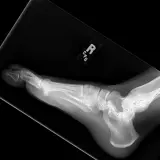

Over 2,100 interactive radiology cases, curated by radiologists for your level of training. Scroll, window, and view cases full screen — just like on PACS. Click linked findings in each writeup to jump straight to them on the image. Cases include sample reports, a focused discussion section, original illustrations, and videos.

Casos totalmente interativos com as ferramentas que você espera em um PACS — rolagem, ajuste de janela, zoom, movimentação, medidas, ROIs e modo de tela cheia.

Anotações detalhadas destacam os achados principais diretamente nos casos. Clique nos achados vinculados nas descrições dos casos para ir ao local exato no exame.